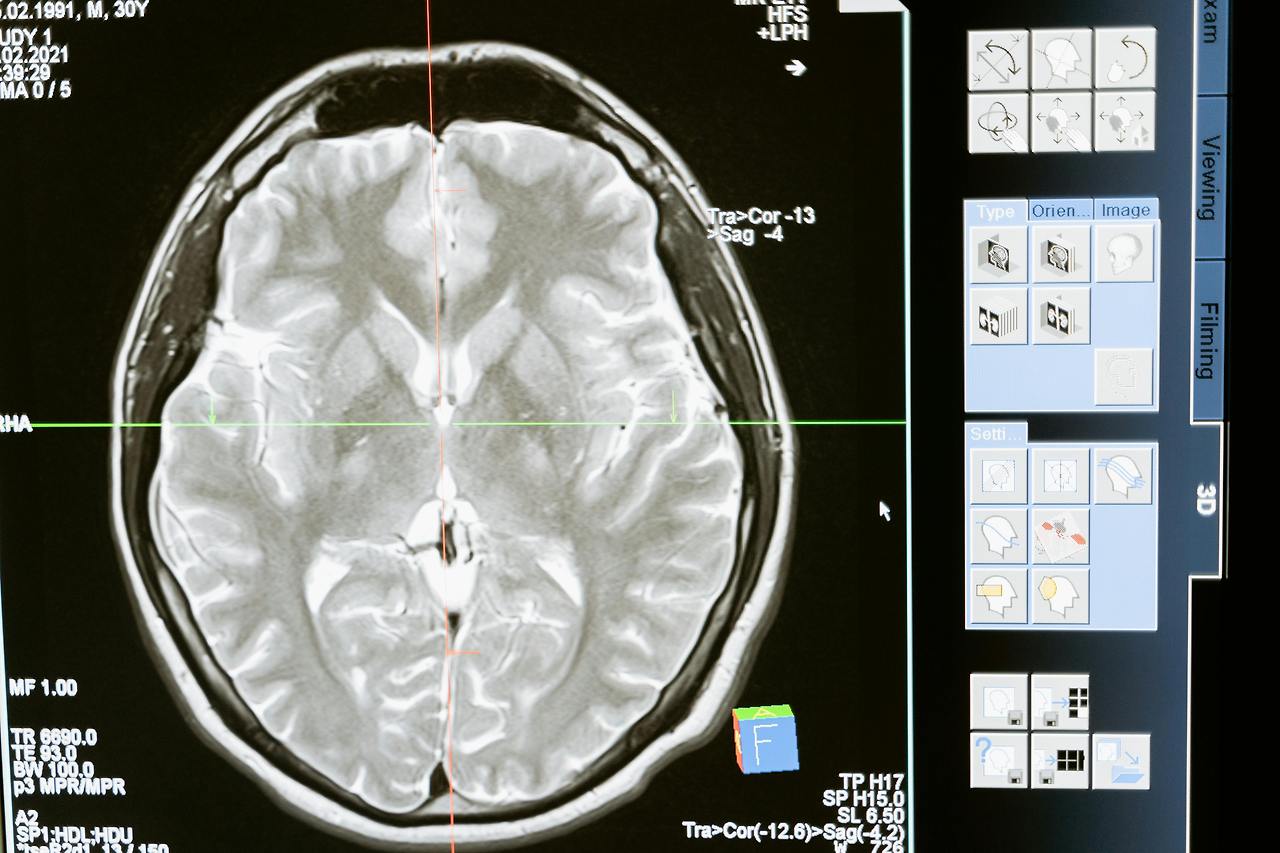

최근 연구에 따르면, 이런 자기 참조 현상은 뇌의 특정 부분과 깊은 관련이 있다고 해요. 특히 사회 불안 장애와 같은 정신 건강 상태에서는 자기 참조 처리가 과도하게 활성화된다고 합니다.

구체적으로 뇌의 중간선 구조, 특히 전측 대상피질(mPFC)후대상피질(precuneus)이 과도하게 활성화된다고 해요. 이 부분들은 우리의 자아 인식과 관련된 활동을 조절하는 기본 모드 네트워크(DMN)의 일부입니다.

이 연구에서는 또한 사회 불안 장애가 있는 사람들이 부정적인 피드백에 더 민감하게 반응하는 특성이 전두엽-두정엽 네트워크의 활동과 관련 있다는 사실을 밝혀냈어요.

특히 전측 대상피질의 과도한 활성화가 제가 새로운 상황에서 느꼈던 그 불안감과 연관되어 있다는 점, 그리고 후대상피질이 과거의 부정적 경험을 계속해서 떠올리게 만들었다는 점이 제 경험과 정확히 일치했어요.